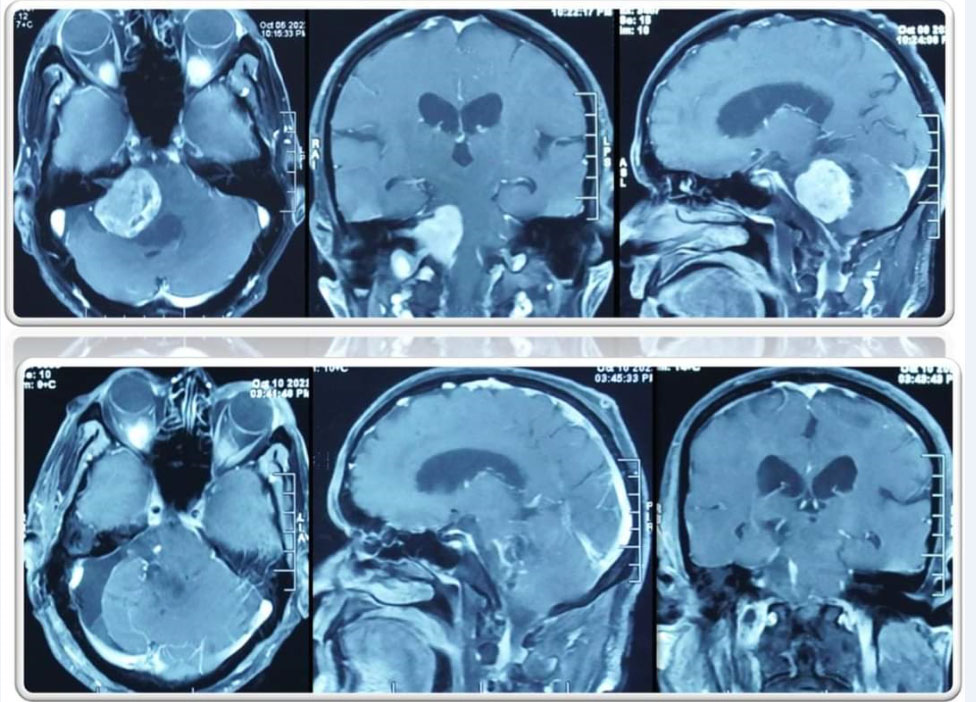

Removal of a large tumor behind the eye, which may be as large as the entire orbit, is a very challenging and complicated operation.....